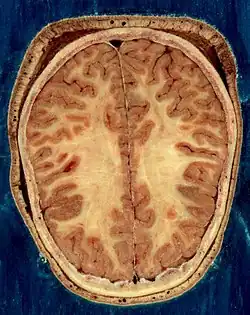

Horizontal section of the head of an adult female human, showing skin, skull, and brain with gray matter (brown in this image) and underlying white matter

The nervous system of vertebrates (including humans) is divided into the central nervous system (CNS) and the peripheral nervous system (PNS).[16] The CNS is the major division, and consists of the brain and the spinal cord.[16] The spinal canal contains the spinal cord, while the cranial cavity contains the brain. The CNS is enclosed and protected by the meninges, a three-layered system of membranes, including a tough, leathery outer layer called the dura mater. The brain is also protected by the skull, and the spinal cord by the vertebrae.

The vertebrate nervous system can also be divided into areas called gray matter and white matter.[19] Gray matter (which is only gray in preserved tissue, and is better described as pink or light brown in living tissue) contains a high proportion of cell bodies of neurons. White matter is composed mainly of myelinated axons, and takes its color from the myelin. White matter includes all of the nerves, and much of the interior of the brain and spinal cord. Gray matter is found in clusters of neurons in the brain and spinal cord, and in cortical layers that line their surfaces. There is an anatomical convention that a cluster of neurons in the brain or spinal cord is called a nucleus, whereas a cluster of neurons in the periphery is called a ganglion.[20] There are, however, a few exceptions to this rule, notably including the part of the forebrain called the basal ganglia.[21]